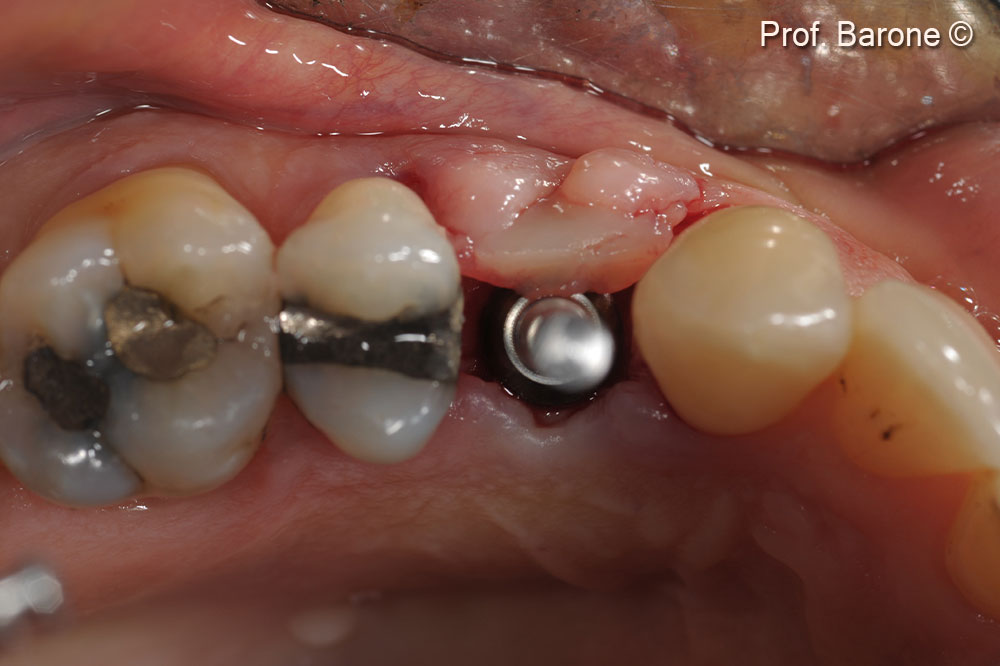

Tooth extraction and use of a surgical guide to measure vertical bone changes throughout the time